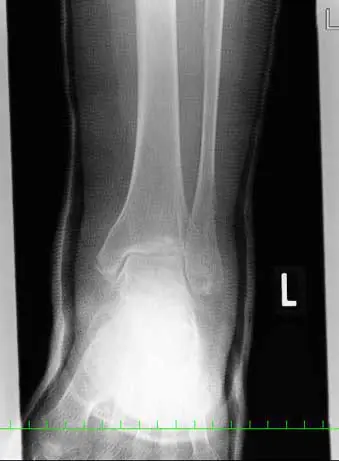

(図1)単純レントゲン像

足関節内外果、脛骨天蓋部に骨折と踵骨アキレス腱付着部より1.5cm近位に骨片を認める。